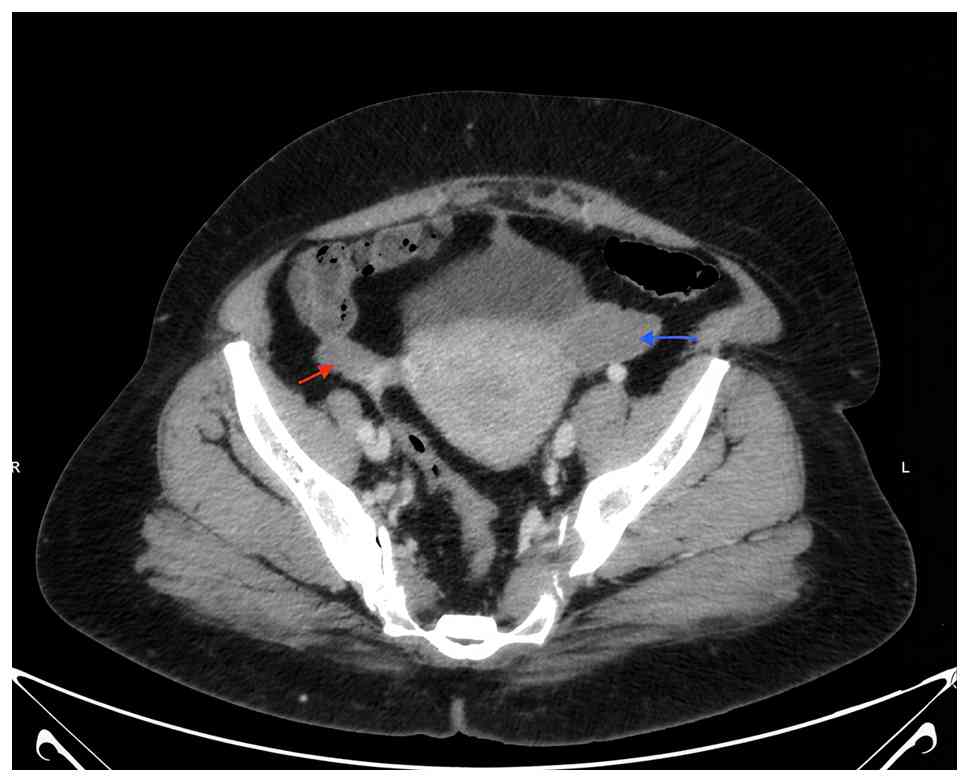

Follow-up and outcomes

The patient undergoes regular follow-ups to monitor her treatment response and disease progression. A CT scan after the third cycle revealed a partial response (Fig. 7). Thus far, she remains stable, with no reported complications or adverse effects from therapy. Her condition is being closely monitored to ensure optimal management.

Axial contrast-enhanced computed

tomography scan (delayed phase) demonstrating bilateral enhancing

ovarian tumors (right ovarian tumor, red arrow; left ovarian tumor,

blue arrow).

Figure 7

Axial contrast-enhanced computed tomography scan (delayed phase) demonstrating bilateral enhancing ovarian tumors (right ovarian tumor, red arrow; left ovarian tumor, blue arrow).